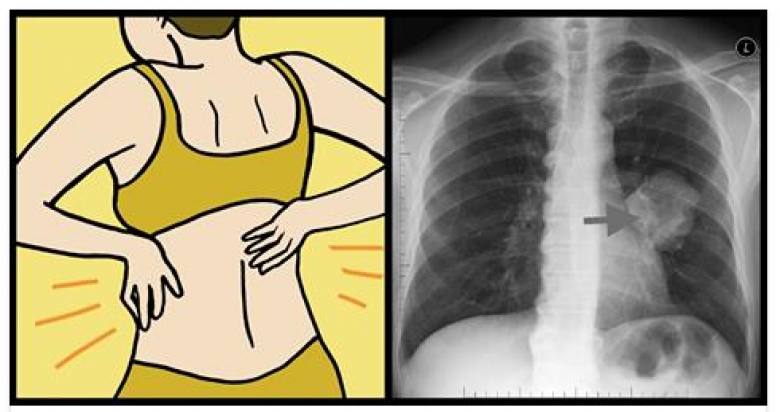

4. Մեջքի և ուսերի ցավեր

Հավանաբար դուք չեք կապում մեջքի ցավերը թոքերի հետ, սակայն կանանց մոտ մեջքի և ուսերի հատվածում սուր ցավերը կարող են ուղիղ կապ ունենալ շնչառական համակարգի խնդիրների հետ: Պատճառն այն է, որ կանայք ավելի հակված են ունենալ թոքերի քաղցկեղի ադենակարցինոմա տարատեսակը: Քաղցկեղի այս տարատեսակի ուզուցքներն առաջանում են թոքերի արտաքին շերտերում և կարող են ճնշում գործադրել կողոսկրերի և ողնաշարի վրա:

8. Ցավեր կրծքավանդակում

Ադենակարցինոման ունենում է փոքր ինչ այլ ախտանշաններ, քան թոքերի քաղցկեղի այլ տարատեսակները: Այն կարող է առաջացնել ցավեր կրծքավանդակում, ինչպես նաև մեջքի հատվածում: Այնպես որ, եթե դուք ունեք շարունակական ցավեր կրծքավանդակի հատվածում շտապեք այցելության գրանցվել բժշկի մոտ: